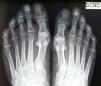

Un varón de 44 años de edad presentaba unas prominencias a ambos lados de las uñas del quinto dedo del pie, que aparecieron después de una caminata en la que llevaba un calzado ajustado. El paciente aquejaba molestias solamente con la presión en esa zona. A la exploración clínica se apreció una rotación externa del quinto dedo y un aumento de tamaño en anchura de la lámina ungueal de ambos dedos pequeños. Así mismo, cada una de estas uñas estaba cubierta por cutícula, dividida por una hendidura longitudinal y, en la parte lateral, la lámina ungueal estaba engrosada (fig. 1a y fig. 2a). La dermatoscopia confirmó que la uña constaba de 2 partes bien delimitadas (fig. 1, fig. 1b y fig. 2b). El paciente no reconocía la presencia de esta alteración en ningún familiar. Se solicitó una radiografía simple anteroposterior y lateral de ambos pies, que descartó la presencia de falanges accesorias y otras alteraciones óseas (fig. 3). No se indicó ningún tratamiento, salvo reducción del traumatismo directo.

Es infrecuente encontrar alteraciones en las radiografías del quinto dedo del pie. En 10 radiografías realizadas en una serie solo 3 pacientes presentaban una vaga «Y» en la punta de la falange distal, y otro paciente una excrecencia ósea tipo espina4. En 2 pacientes se identificó la forma en «Y» de la zona distal de la última falange durante la cirugía4.